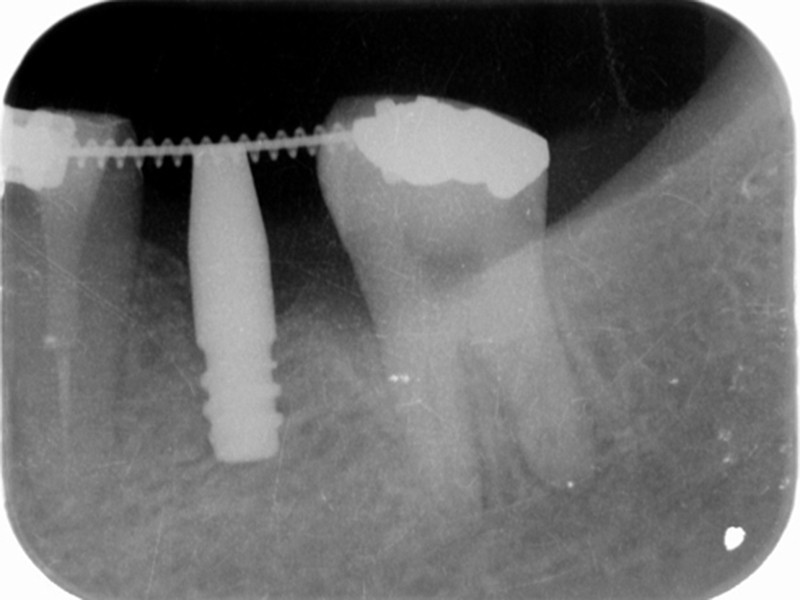

▼ ケース4.Upright症例

初診

治療中